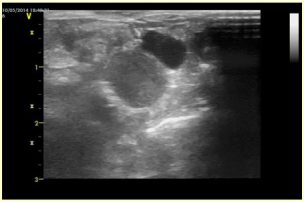

卵巣・子宮疾患はX線検査や超音波検査で判断します。

卵巣・子宮の病気以外にも膀胱結石や膀胱炎なども考えられるので、尿検査なども行います。 腎臓や膀胱からの血尿だと薄い血尿になり、子宮疾患であると鮮血です。